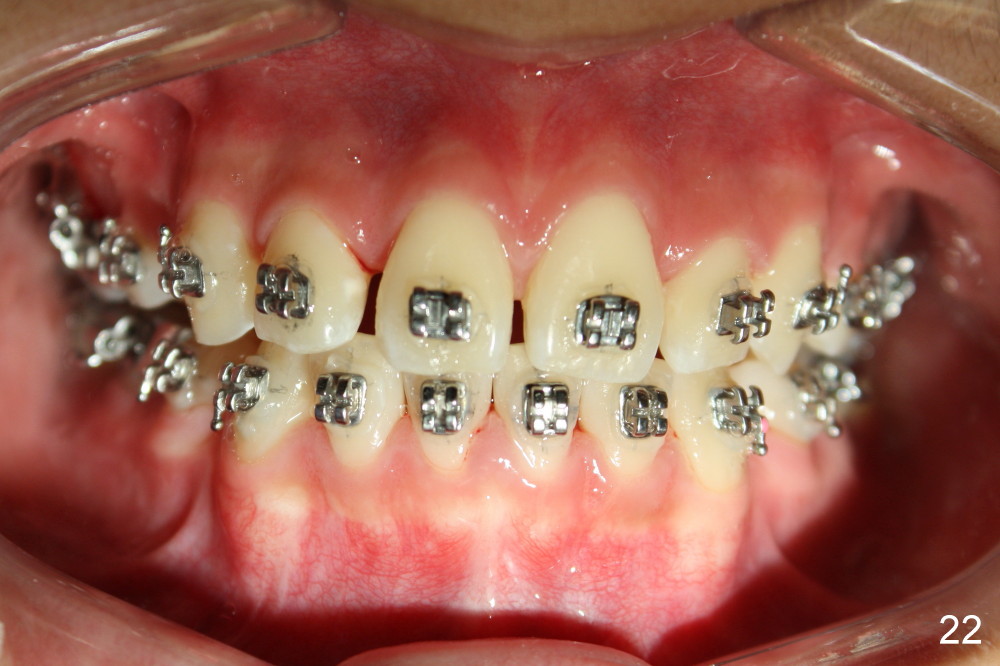

Four and a half months post bracketing (Fig.21-25), what do you find and what should be done next?

Prior to bracketing, the mesiodistal space for #18 is planned to be obtained by moving #20 and then #19 mesially (Fig.31-35, 16x16 ss). The six anterior lower teeth are tied together in a figure 8 fashion. Power chains are placed between the lower canine and the 2nd bicuspids. The upper diastemata are to be closed by power chains between the 1st molars.